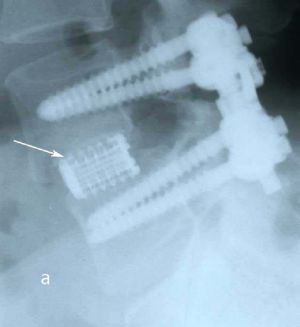

При рентгенографии (Рис.7) и МРТ (Рис.8) поясничного отдела позвоночника выявляется дегенеративный ретролистез L5 позвонка, секвестрированная парамедианная грыжа мп диска L5-S1 слева.

| Рис. 7а,b. Рентгенограмма поясничного отдела позвоночника в боковой (а) и прямой (b) проекциях до операции. Стрелкой показано смещение тела L5 позвонка кзади. | |

Пациенту выполнено оперативное лечение: удаление секвестрированной парамедианной грыжи мп диска L5-S1 слева из минидоступа, миниинвазивная транспедикулярная фиксация L5-S1 титановой конструкцией.

При контрольной рентгенограмме отмечено правильное положение транспедикулярной системы и кейджа на уровне L5-S1 позвонков. (Рис.9)